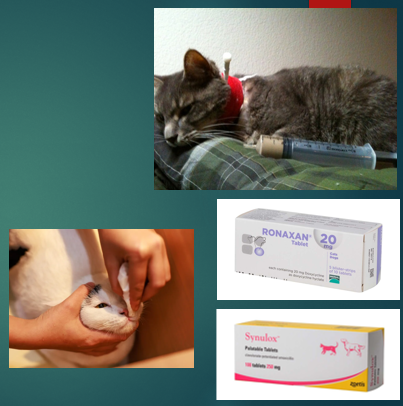

Treatment of cat flu

Isolated - infectious

Antibiotics → Bordetella bronchiseptica, Chlamydophila, Secondary infections

Anti-viral medication

Fluid therapy

nutrition

Mucolytics

Nursing care - grooming is very important in these cases, cleaning the face and eyes regularly to get rid on the mucous is really important

Mucolytics

Helps to break down discharge